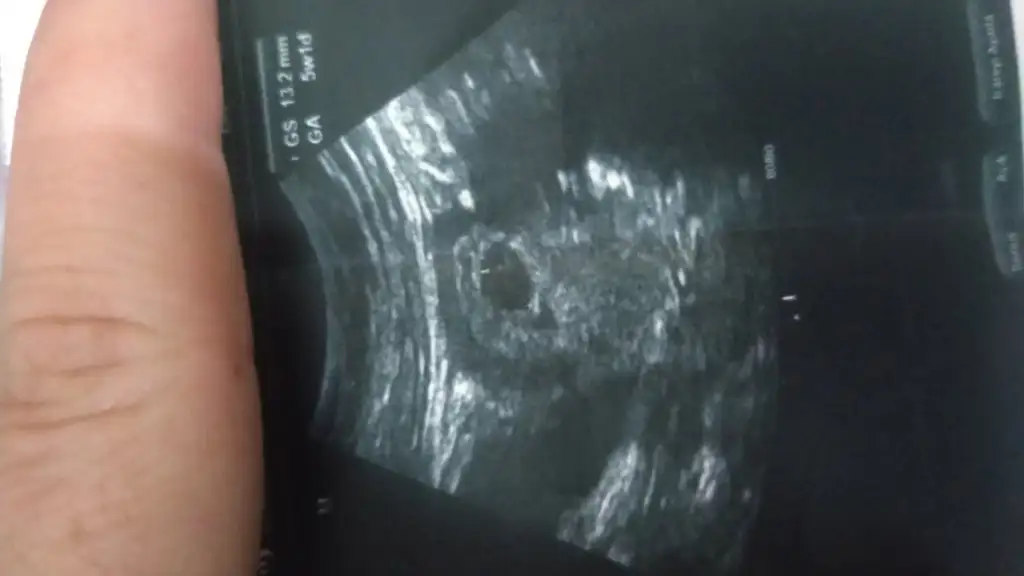

Buradan anlaşılır mı bilmiyorum. Biraz koyu oluyor ya fotoğrafta. Doktor demedi mi bu konuda bir bilgiFotoğraf atsam anlar mısınız

Kanama küçük dedi sadece onun dışında bi şey demedi karnımdan çekildi telefonu çevirince solda kanama varBuradan anlaşılır mı bilmiyorum. Biraz koyu oluyor ya fotoğrafta. Doktor demedi mi bu konuda bir bilgi

Parlak alan sanırım kanama olan yer. Kesenin beslenmesine engel olacak bir yer değil. Bol bol dinlenin. Ayağınızın altına yastık koyun. Progestan ver mi ya da iğne vurdu mu sizeKanama küçük dedi sadece onun dışında bi şey demedi karnımdan çekildi telefonu çevirince solda kanama var

Kesenin yanındaki koyuluk değil mi kanama alanıParlak alan sanırım kanama olan yer. Kesenin beslenmesine engel olacak bir yer değil. Bol bol dinlenin. Ayağınızın altına yastık koyun. Progestan ver mi ya da iğne vurdu mu size